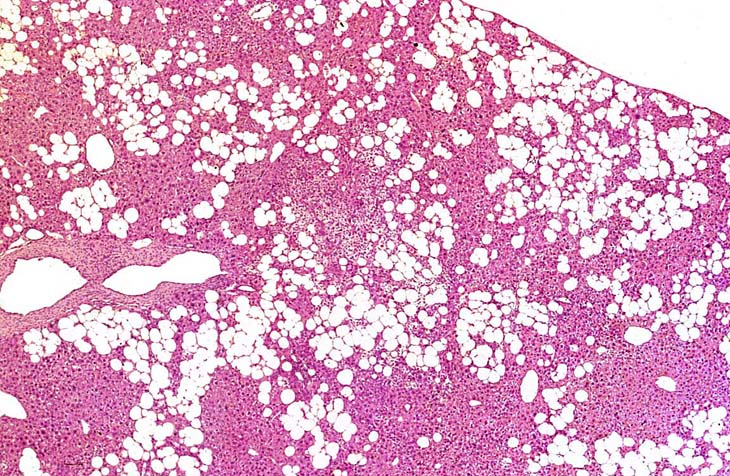

This Ito cell tumor is comprised of a mixture of stellate cells and mature adipocytes.